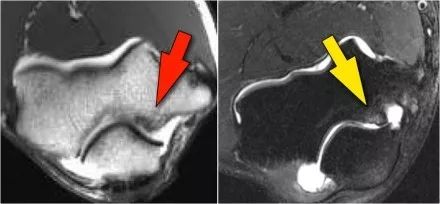

外翻过度综合征的关节病由于外翻过载,在肱骨-尺骨关节的后内侧部分存在剪切力。注意在T1W图像上看到的软骨下硬化(红色箭头)。在T2W图像上存在软骨下骨髓水肿和软骨损失(黄色箭头)。